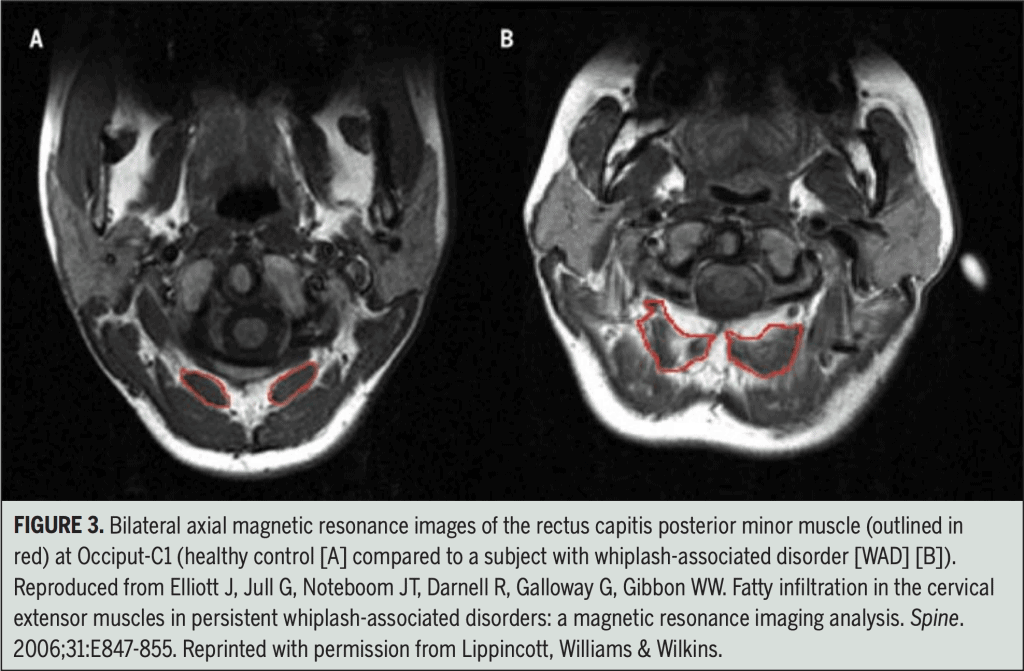

Within weeks of sustaining a neck injury, deep neck muscles begin to weaken and areas of fatty infiltrate are visible on MRI. These changes are present even after symptoms are gone and when recovery is typically considered complete.8